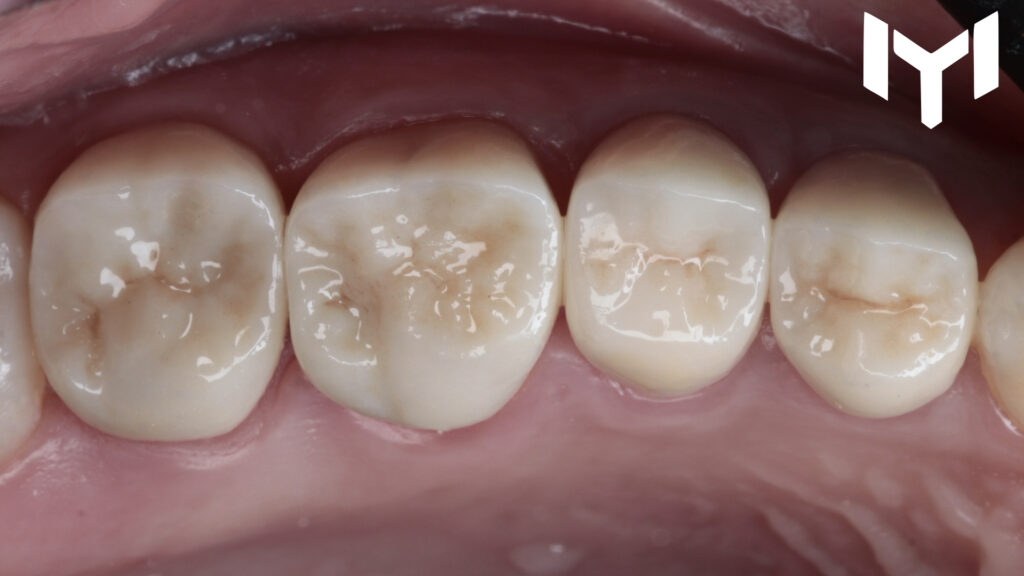

2. The Power of Temporization The “magic” happens during the healing phase. We placed high-quality provisional crowns for one month. This stage is crucial for:

• Guiding the gingival healing.

• Determining the ideal emergence profile.

• Ensuring the patient’s comfort and function before the final stage.